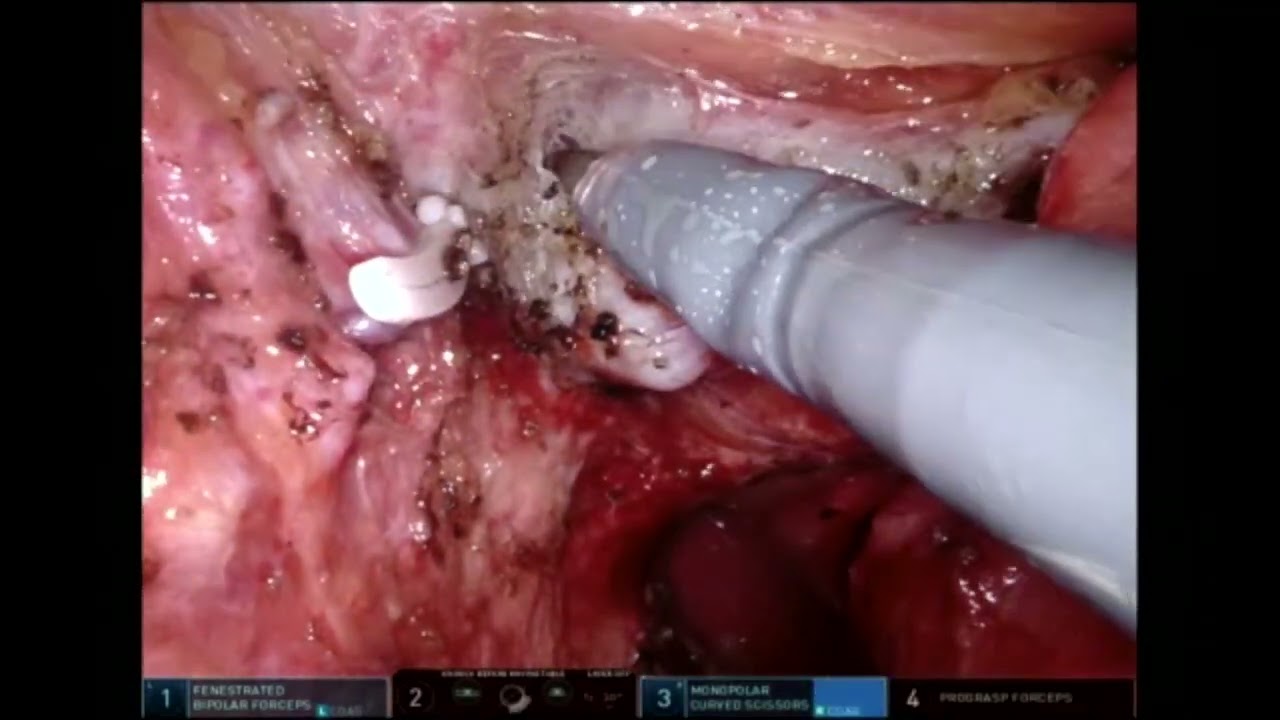

PSMA Radio Guided Surgery in Primary Prostate Cancer

Robot-assisted radioguided surgery using a DROP-IN gamma probe